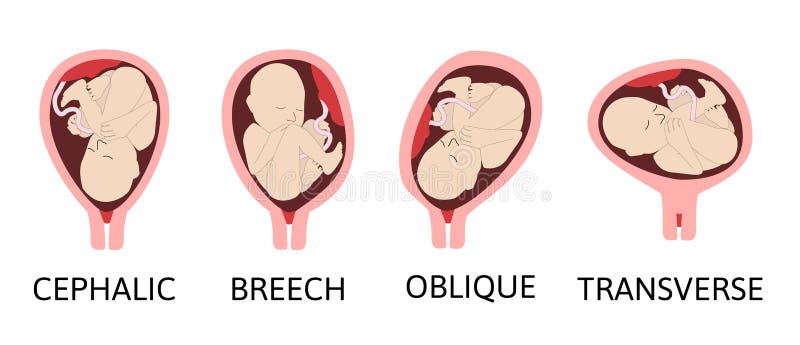

Во время беременности, положение плода имеет большое значение для мамы и малыша. Одним из типичных положений является продольное предлежание головное. В этом положении голова малыша находится внизу, а ножки - наверху. Это положение достаточно распространено и предпочтительно для естественных родов.

Фото положения плода во время беременности

Ниже приведены несколько фотографий, которые помогут вам визуализировать положение плода во время беременности.